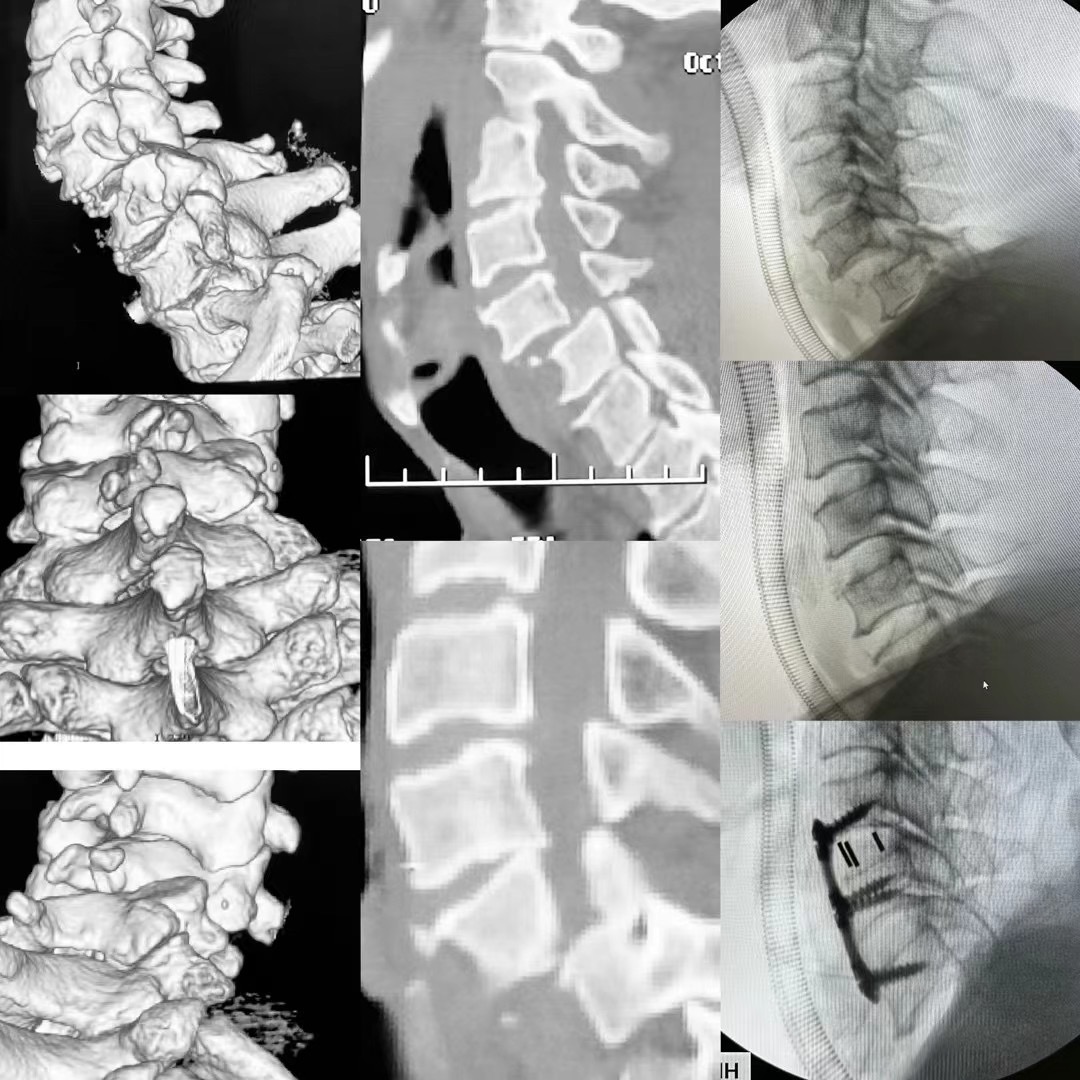

近日,骨二科臧全金副主任医师团队成功完成一例复杂脊柱手术。患者为颅底凹陷症合并脊柱侧凸,已经在西安多家医院门诊就诊,并在某知名三家医院住院治疗,但均未获得良好诊治。后来在北医三院主任医师推荐下来到臧全金副主任医师处治疗。接诊后,臧全金发现患者为严重的颅底凹陷症合并脊柱侧弯,实属罕见,治疗难度大,风险高。但正是这样的病例激起了他的兴趣,术前其带领的治疗团队详细研读了患者的影像资料,制定了详尽的手术方案,于近日一期完成了颅底凹陷症的解剖复位和脊柱侧凸截骨矫形术,术后患者恢复良好,无任何神经并发症。颅底凹陷症合并寰枢椎脱位、脊柱侧凸两种疾病任何任何一种在脊柱外科都属于高难度复杂手术,在脊柱外科领域都属于珠穆朗玛峰般的存在,西北地区只有少数几家三甲医院开展此类疾病的手术治疗,而能够主刀完成这种手术的医生少之又少。看到孩子顺利完成手术,患者家属感到特别高兴,再三感谢臧全金副主任医师团队高超的手术技艺以及过人的胆识,为自己的孩子解决了困扰多年的疾病。

像这样的高难度颈椎手术,臧全金副主任医师带领曹凯博士、郭帅博士的团队近期已完成了多例,均取得了良好的手术效果。一例外省的颈椎肿瘤患者,慕名从省外来到骨二科,在臧全金副主任医师团队的精心治疗下,一期前后路切除肿瘤,完成颈椎重建,术后神经功能得到恢复。多例颈椎后纵韧带骨化患者,椎管内占位达到椎管前后径的70-80%,脊髓被压得只剩下一条线,臧全金带领的团队精雕细琢,为患者完成减压,术后患者从蹒跚行走到灵活小跑;颈椎间盘突出压迫脊髓瘫痪患者在臧全金团队的治疗下从卧床到下地行走…………为了解决患者的病痛,臧全金急患者之所急,近一周从家中赶往医院为两次颈椎脱位脊髓损伤患者行急诊手术,第一时间挽救患者脊髓功能。很多病例不一例数。

作为骨科最年轻的带组副主任医师,臧全金在过去的六年里带领治疗团队完成了科室的近半疑难病例及危重患者,同时精细研究业务,配备了自己的手术放大镜和术中录像系统,将手术风险、创伤降低的同时提高了治疗效果,目前颈椎前路手术可在三至四厘米切口下高质量完成的同时出血量控制在几十毫升,寰枢椎脱位手术在一小时左右完成切开复位固定,颈椎后路手术也在1.5小时左右完成,总体出血量越来越少。